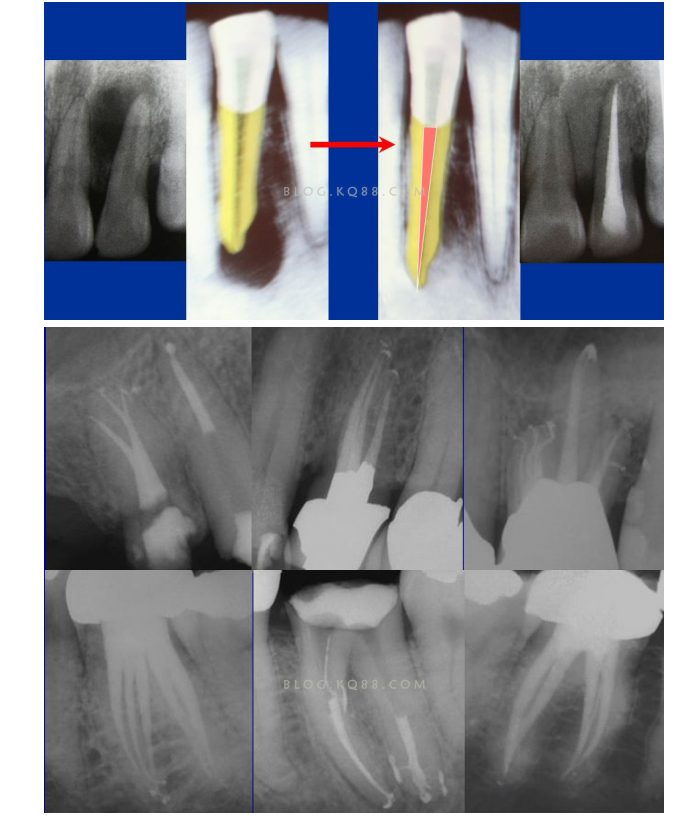

1簡化難度 一個牙齒的根管治療難易程度不單單是根管的彎曲、細(xì)小、牙位、是否再治療決定的,開髓的直線進(jìn)入和根管口的預(yù)先恰當(dāng)處理可以簡化很大的難度,開髓是根管成敗的基礎(chǔ)。對于彎曲根管冠部的直線入口就顯得尤為重要,冠部良好的直線入口可以避免側(cè)穿、臺階、遺漏根管等問題的發(fā)生,冠部直線入口形成的良好情況,取決于醫(yī)生的理念和合理的器械選擇。開髓孔的大小不是由醫(yī)生和患者的意愿決定的,而是由要治療牙齒的髓腔大小決定的。

2相信有更多的根管存在 相信根管的數(shù)目比我們想象的多,根管系統(tǒng)的復(fù)雜程度比我們想象的見到的要更復(fù)雜,我們只有用盡所有努力和辦法才可能達(dá)到預(yù)期目標(biāo),對于上 牙合 6的MB2來說過去是偶爾有,現(xiàn)在是偶爾沒有,各種文獻(xiàn)報道的比例也不一致,我在培訓(xùn)班醫(yī)生帶來的離體牙中幾乎沒有見到?jīng)]有的,臨床中也是一樣。對于尋找的方法來說,我覺得相信有才是最重要的,首先相信一定有就會想各種辦法,找到的幾率就會更多。如果有條件在顯微鏡和超聲的配合下效率會更高。

5、預(yù)備到多少號結(jié)束根管預(yù)備理想的情況應(yīng)該預(yù)備到多大錐度,多少號,預(yù)備后根管空間是金字塔還是埃菲爾鐵塔。專家經(jīng)過離體牙根尖切片研究發(fā)現(xiàn)根尖狹窄部遠(yuǎn)比想象的要大,如果根管預(yù)備太小就會殘留感染物,根管的部分空間就不會預(yù)備到,殘留的感染物就會造成治療效果達(dá)不到預(yù)期目標(biāo)。只有做到了充分的預(yù)備,盡可能的多沖洗才會有好的結(jié)果。

根管治療要做到看清楚,去干凈,充恰滿,封嚴(yán)密,就會達(dá)到期望的結(jié)果。2200年前的病例只充填了冠1/3可以理解、可以接受;2200年后的今天我們有先進(jìn)的設(shè)備和材料,就要充填出大錐度高密度的完美結(jié)果。理念決定技術(shù),標(biāo)準(zhǔn)決定技術(shù)的提高和進(jìn)步。